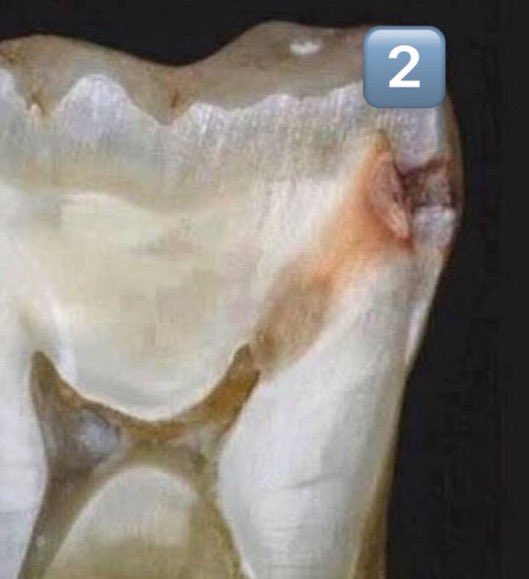

هذه التسوسات عادة تحدث اذا لم تستخدم الخيط السني بإنتظام..وهذا النوع "الخفي" من التسوس يحتاج اكتشاف مبكر عن طريق أشعة من نوع خاص(الصورة ١)وتعمل هذه الأشعة عادة كل ٦ أشهر خلال الفحص الدوري.. الصورة ٢: مقطع عرضي لتسوس مايين الأسنان

٩/تطور التسوس مابين الأسنان:

يتطور التسوس من المينا إلى العاج ويمكن في هذه المرحلة الشعور ببعض الألم خاصة عند أكل السكريات ولكن هذا ليس دائما ولا يمكن الإعتماد على هذا الإحساس أو انتظاره لمراجعة الطبيب

١٠/مرحلة سرعة تقدم التسوس بين الأسنان:

عند وصول التسوس للعاج وبحكم كون مادة العاج أقل صلابة وأكثر رطوبة ووفرة في الماء يكون إنتشار التسوس في هذه المرحلة أسرع بكثير و ربما يتطور الألم بشكل متسارع خاصة أنه أصبح أقرب للب وعصب الأسنان